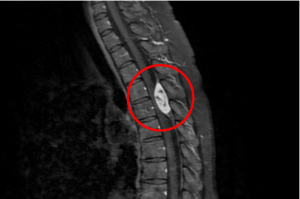

罕見脊椎血管瘤差點致癱瘓 術後積極復健恢復健康

38歲廖小姐因連日腹瀉不止由花蓮慈濟醫院腸胃內科收住院治療,但在準備出院前一天,雙腳竟完全無法移動,經核磁共振檢查,發現她的胸椎第四、五節空腔有顆三公分大的腫瘤,已嚴重壓迫神經。隨即轉由神經外科部神經血管介入治療科主任李建輝,以手術清除腫瘤治療,三週後即可靠輔具行走,目前恢復良好。